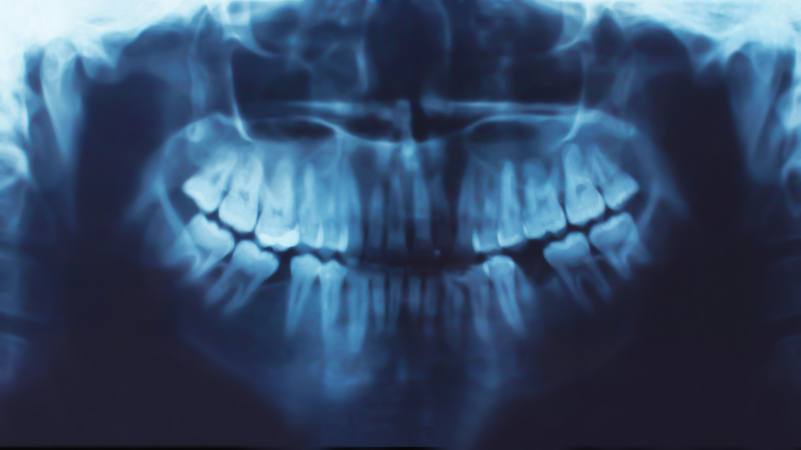

Family Dentist Worcester: Your Child’s First Dental Visit and What to Expect Read More February 1, 2020